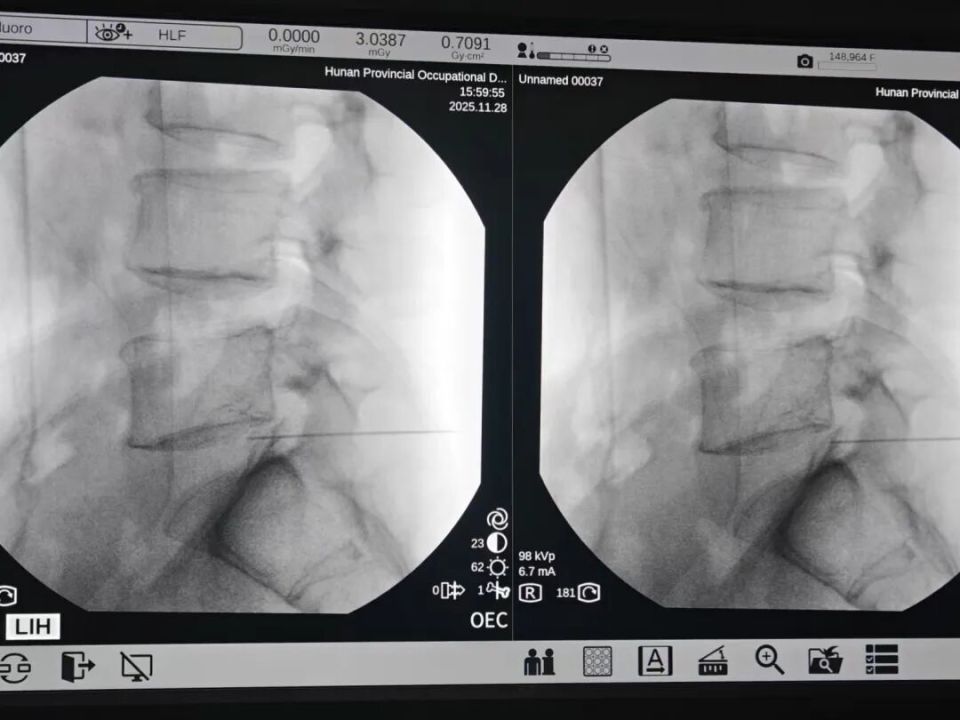

在湖南省职业病防治院(南华大学附属职业病防治院)就诊后,彭先生被确诊为 腰椎间盘突出。考虑到他需要长期驾驶的职业特性,且保守治疗效果不佳,医生建议行 “腰椎射频消融术”。手术当天,他的腰痛即明显缓解。彭先生感叹:“原来以为一定要开刀,没想到微创也能解决问题!”

对于因腰椎间盘突出引起、且保守治疗无效的腰痛,射频消融术是一种针对性强的微创解决方案。它尤其适合需快速返岗的久坐族,其核心优势源于独特的 “精准热疗” 机制。

正因为创伤极小(仅一个针眼)、目标精准,手术通常在30-60分钟内完成,且仅需局部麻醉,术后当天疼痛显著缓解,次日即可下床活动,约两周可恢复驾驶、伏案等轻体力工作,完美契合久坐族快速回归生活和工作的需求。